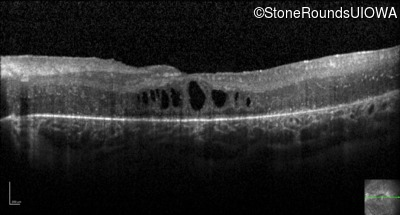

Optical Coherence Tomography - Right - 20/80 -1

Exemplar / OCT Stack